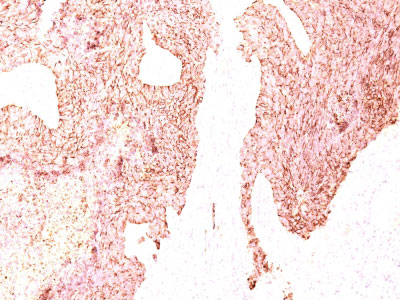

Formalin-fixed, paraffin-embedded human Adrenal Gland stained with Chromogranin A Monoclonal Antibody (LK2H10)

Formalin-fixed, paraffin-embedded human Small Cell Lung Carcinoma stained with Chromogranin A Monoclonal Antibody (LK2H10) |